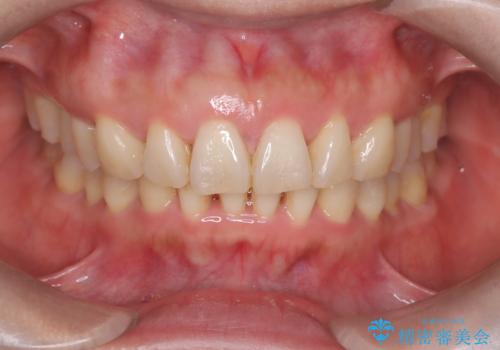

【インビザライン】出っ歯を治したい

- 前歯が出ていることを主訴に来院されました。

インビザラインにて臼歯部の遠心移動及びIPRを行なっています。

叢生量が多いケースでしたが、綺麗な歯並びとなり患者様にも満足していただきました。

非抜歯矯正のため口元の変化はありません。